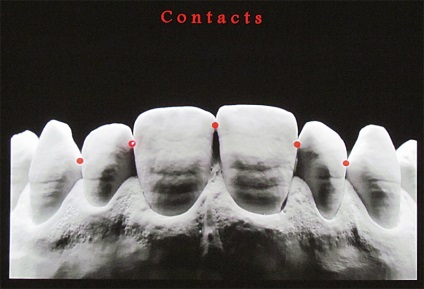

A domború részét az érintkező felületek szintjén a legnagyobb szélessége a koronát képez két homlokegyenest kapcsolattartó pontok találhatók különböző magasságban. Két szomszédos érintkezési pontja két szomszédos fogak tartalmazhat egy kapcsolattartó pont, amelynek területe egyenlő a kb I mm-elülső fogak.

Annak ellenére, hogy két szomszédos korona szemközti fogak különböző magasságú, a vele érintkező pont az érintkező felületek találhatók ugyanazon a szinten. Ez az eljárás biztosítja a fogazat különböző konvex medialis és laterális / távoli felületek. Fang, kivételt képeznek az egymást követő csökkenése a magassága a fogak korona, az integráció a fogsor által nyújtott speciális formája. Másrészt, a különböző domborulata az érintkező felületek a fogak vezet az a tény, hogy a korona a felső metszőfogak helyzetben laterális és mediális kapcsolattartó pontok különbözik függőlegesen körülbelül I mm oldalsó felületén - közelebb a nyakát a fogak, a mediális felszínén - közelebb áll az élvonalbeli .

Ennek eredményeként, az érintkezési pontok az elülső felső fogak vannak elrendezve egy ív, megismételve a helyzetben a vágóélek vagy meghajlítjuk a felső széle az alsó ajak. Az alábbiakban, mind a felső fogazat a kapcsolattartó pont a kettő között metszőfogak.

A kapcsolattartó pontok között, a felső elülső fogak elrendezve egy görbe mentén, megismételve a hajlam a vágóélek a felső és alsó ajak kontúr. Ha az érintkezési pont között a metszőfogak és a szemfogak vetített középvonalában, akkor hogy három szinten egy pályát körülbelül 1 mm.

Az érintkező felületek részt vesznek a teherelosztás a fogak fölött rágás közbeni deformáció tömörítés állkapcsát. Amikor rágás terhelés koronák deformálódnak a vágási magasság és oldalirányban kiterjedő. Ennek eredményeként az ilyen deformáció koronák jelentős része a terhelés nem csak felszívódik, de átvitt fogazat által sűrűségének növelése érintkezési pontokat. A sűrűsége a kapcsolattartó pontok úgy, hogy változó, attól függően, hogy az erőssége összehúzódása fogazat, és meg kell érteni, hogy sűrűségének meghatározásához kapcsolattartási pontok, mi határozza meg egy nyugalmi állapotban. Ha túlzott deformációját fogak zománc függőleges repedések - világosan jelzi a funkcionális túlterhelés miatt parafunction fogak, fogcsikorgatás.